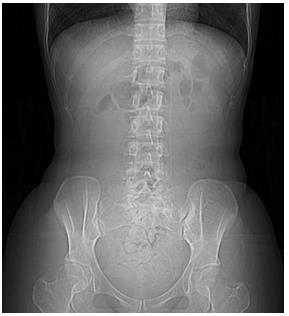

照片5:腹部X 線照片(臥位)

腹部正中間,從盆腔到橫隔膜近傍位置有占位。橫結(jié)腸內(nèi)部有氣體。“蟬蛹”左側(cè)有顆粒狀大便。是乙狀結(jié)腸便。